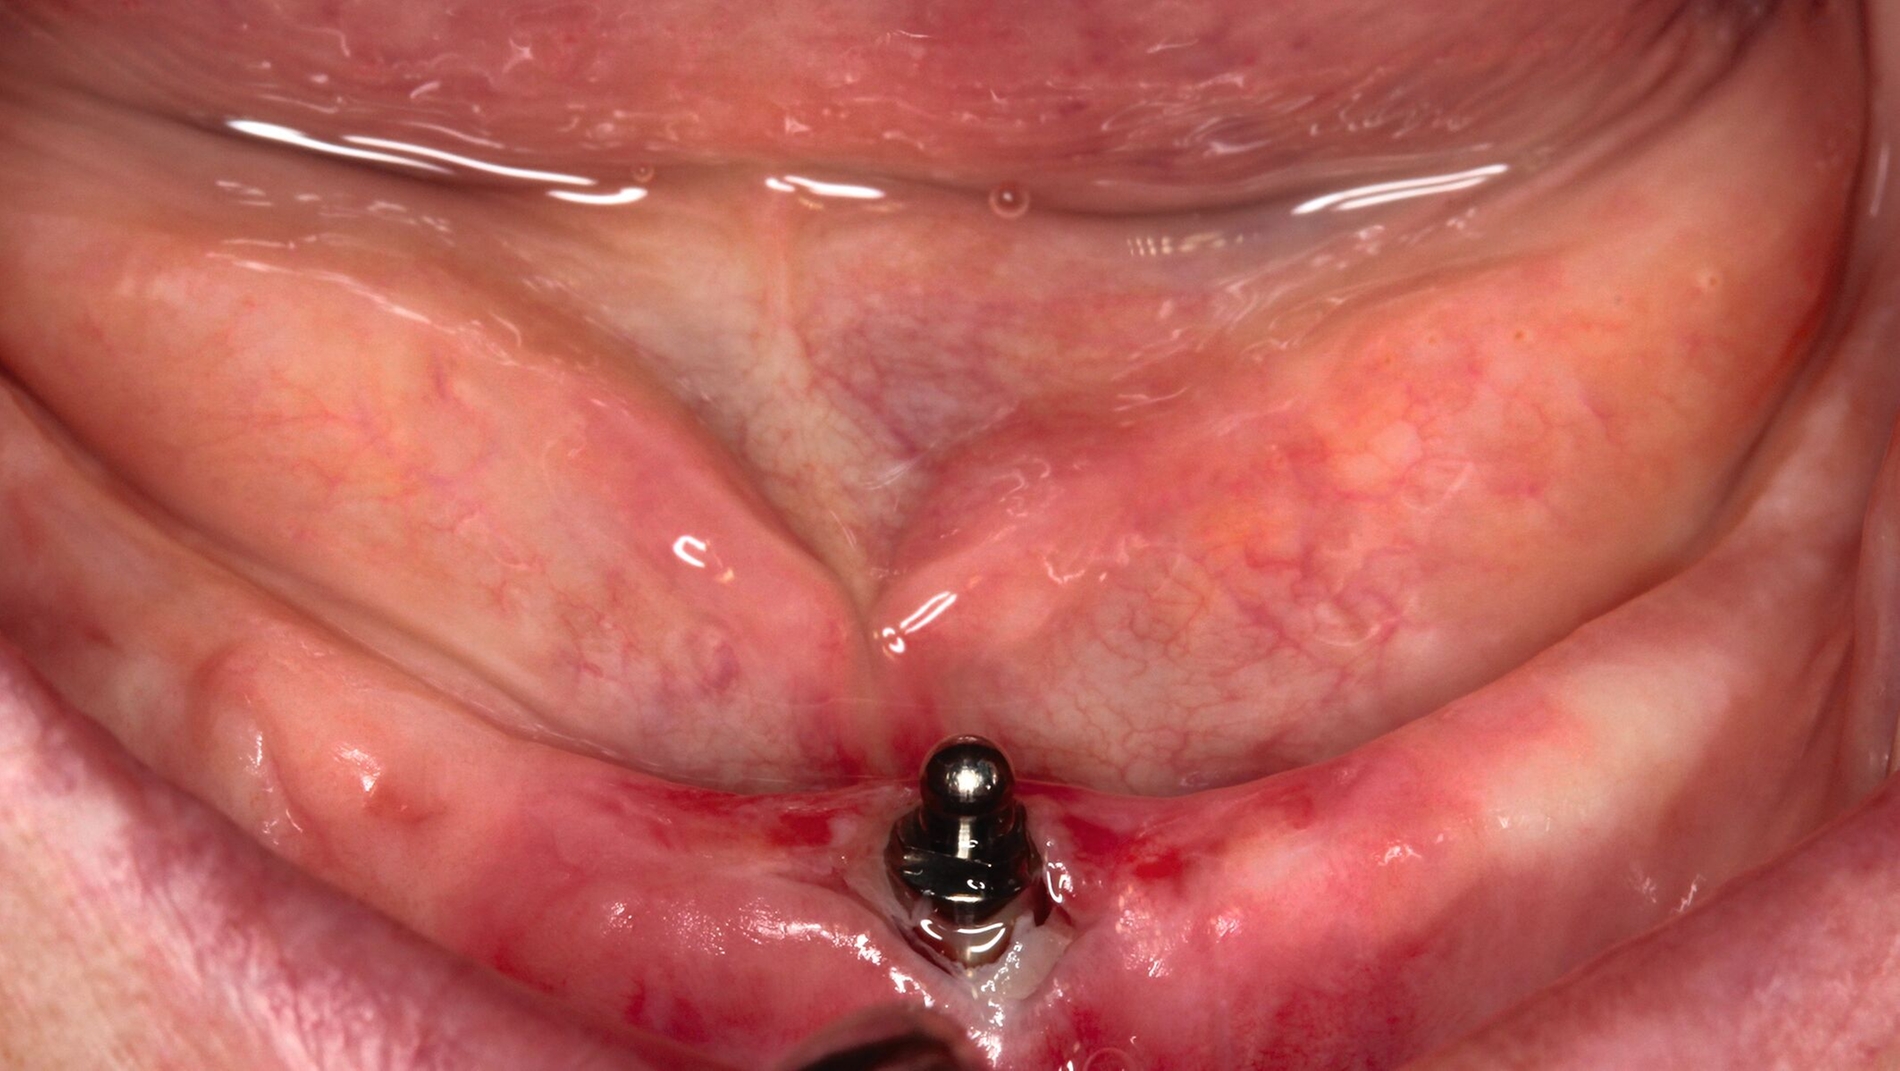

Ein überschaubares, pflegeleichtes und zudem preiswertes Konzept ist das mittig stehende einzelne Implantat zur Stabilisierung der totalen Unterkiefer-Prothese. Die erste Fünf-Jahres-Studie hierzu aus dem Jahr 1997 berichtet über eine Implantatüberlebensrate von 100 Prozent bei 21 Patienten mit einem mittleren Alter von 74,2 Jahren [Cordioli et al., 1997]. Die hohe Implantatüberlebensrate wurde inzwischen von zahlreichen Studien bestätigt [Padmanabhan et al., 2020]. Die Matrizen auf Kugelankern oder anderen Druckknopf-artigen Elementen werden in der Regel kostensparend direkt in die vorhandene Prothese einpolymerisiert (Abbildung 2).

In einer von Kiel initiierten, DFG-geförderten, multizentrischen Studie mit 158 Ein-Implantat-Prothesen war die Implantat-Verlustrate nach fünf Jahren bei Sofortbelastung des Implantats höher als bei Spätbelastung (15,3 Prozent versus 3,8 Prozent) [Kern et al., 2018]. Die neun Implantatverluste in der Sofortbelastungsgruppe traten in den ersten drei Monaten nach Insertion auf. In der Spätbelastungsgruppe musste ein Implantat bei der Freilegung und ein weiteres nach fünf Jahren entfernt werden (Abbildung 3). Die postoperativen Beschwerden waren bei Sofortbelastung höher als nach Spätbelastung [Mundt et al., 2017]. Nach der Prothesenstabilisierung war eine deutliche Verbesserung der Kaueffizienz ohne Unterschiede zwischen den Belastungsprotokollen zu beobachten, die den gesamten Fünf-Jahres-Beobachtungszeitraum anhielt [Passia et al., 2022]. Die Patientenzufriedenheit [Passia et al., 2017] und die mundgesundheitsbezogene Lebensqualität [Schwindling et al., 2018] wurden ebenfalls spürbar verbessert.

Der Nachsorgeaufwand scheint jedoch nicht unerheblich zu sein. Von den über fünf Jahre nachverfolgten 102 Prothesen mussten 37 wegen Prothesenbasisfrakturen repariert werden, darunter elf mehrmals. Weiterhin wurde 123 Matrizeninserts und 14 Kugelköpfe im Studienverlauf ausgetauscht. Mögliche Komplikationen bei Ein-Implantat-Prothesen werden in einer Literaturübersicht mit einer berechneten jährliche Frakturrate von 10,8 pro 100 Kugelanker-Prothesen und 16,8 Nachsorgemaßnahmen pro 100 Locator-Prothesen bestätigt [Padmanabhan et al., 2020]. Die nachträgliche Einarbeitung einer Metallbasis verhindert Basisfrakturen [Pinheiro et al., 2021]. Insgesamt scheint die Ein-Implantat-Prothese im Unterkiefer eine einfache, minimalinvasive und kostengünstige Alternative mit hohen Implantatüberlebensraten bei Spätbelastung für ältere Patienten zu sein, die einem Vergleich mit Zwei-Implantat-Prothesen standhält. Bei der Wahl dieser Therapievariante für den Unterkiefer bei kompletter Zahnlosigkeit sollte der Nachsorgeaufwand berücksichtigt werden. Eine Sofortbelastung des mittig stehenden Implantats bleibt Ausnahmefällen vorbehalten.